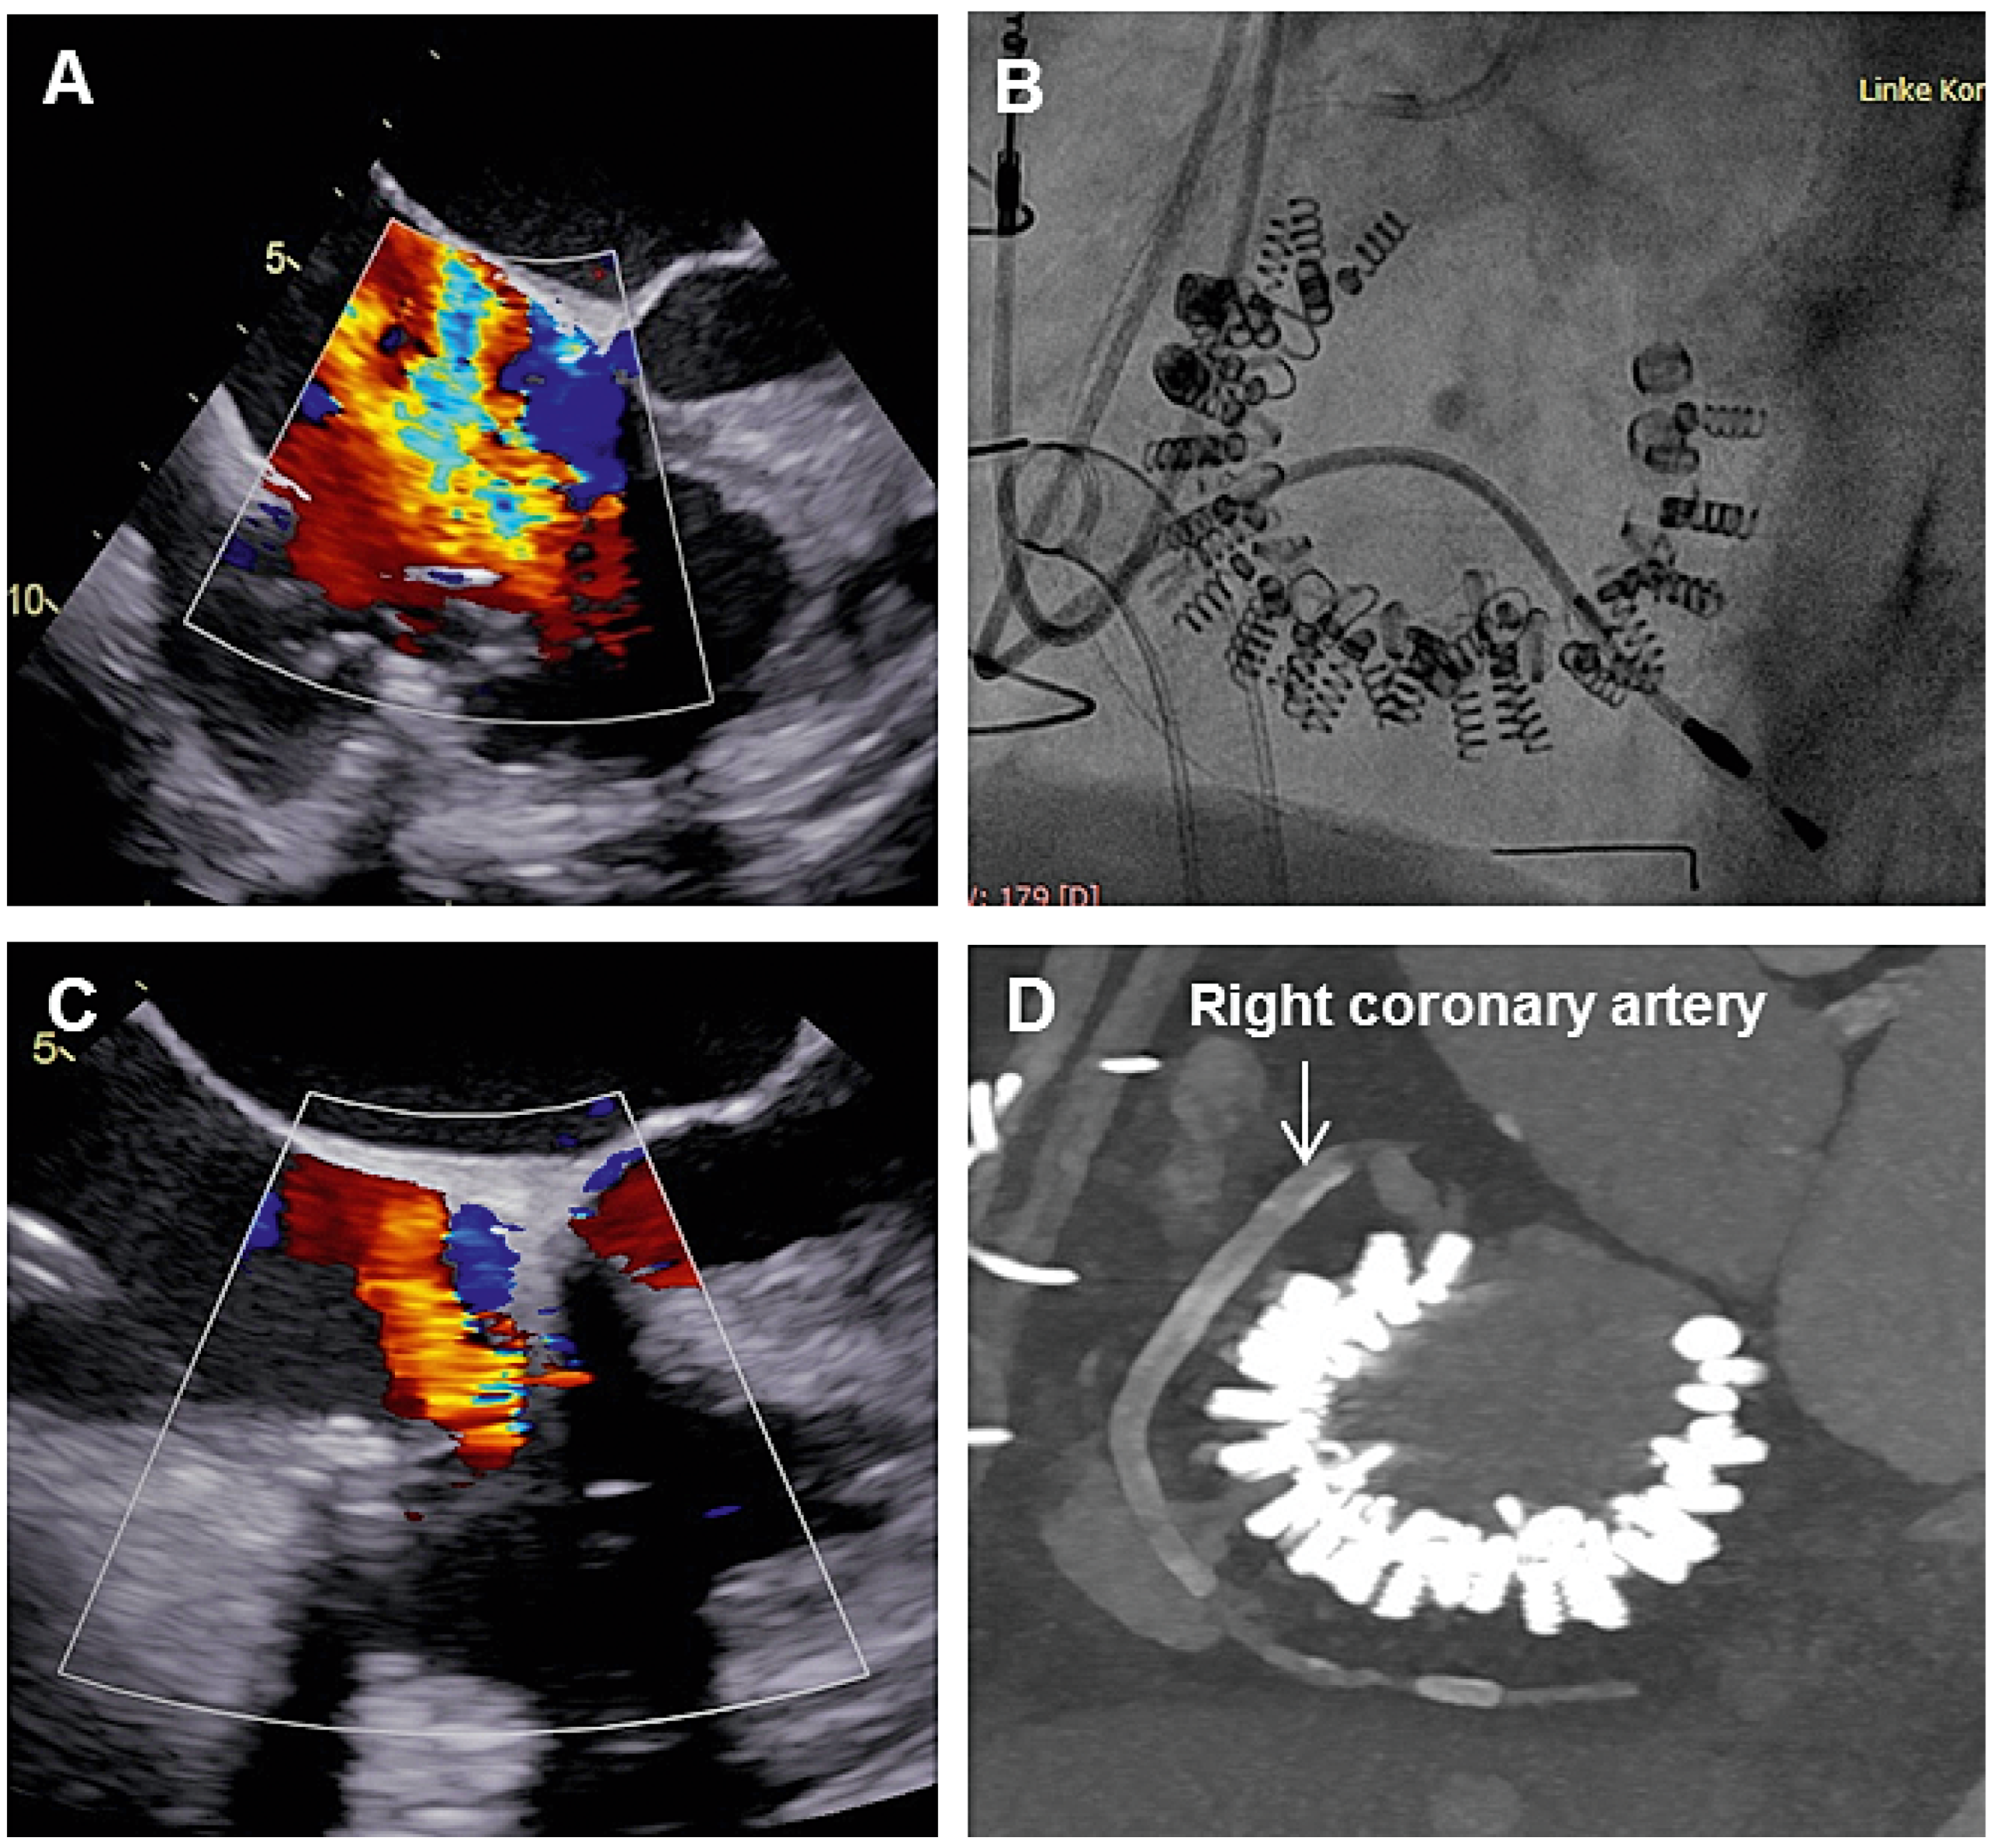

Caval valve implantation